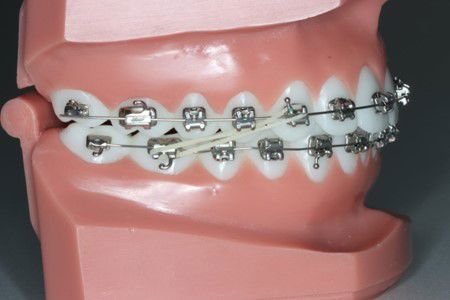

Sidder på tandbånd og fiskestang bruges til at hjælpe hjørnetand frem og ned til tandbuen.